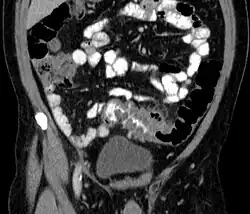

People with the above symptoms are commonly studied with computed tomography, or a CT scan.[37] Ultrasound can provide preliminary investigation for diverticulitis. Amongst the findings that can be seen on ultrasound is a non-compressing outpouching of bowel wall, hypoechoic and thickened wall, or an obstructive fecalith at the bowel wall. Besides, bowel wall oedema with adjacent hyperechoic mesentery can also be seen on ultrasound. However, a CT scan is the mainstay of diagnosing diverticulitis and its complications.[12] The diagnosis of acute diverticulitis is made confidently when the involved segment contains diverticula.[38] CT images reveal localized colon wall thickening, with inflammation extending into the fat surrounding the colon.[39] Amongst the complications that can be seen on CT scan are: abscesses, perforation, pylephlebitis, intestinal obstruction, bleeding, and fistula.[12]